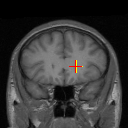

Figure 7: Example comparison among ADDD + inv (c/d), ADDD (e/f), ADD (g/h), AD (i/j) and D (k/l) networks.

In Figure 7, we compare ADDD + inv, ADDD, ADD, AD and D. It shows that network cascading better aligns the images with the presence of large displacement, while the invertibility loss has a remarkable effect on the liver boundary.